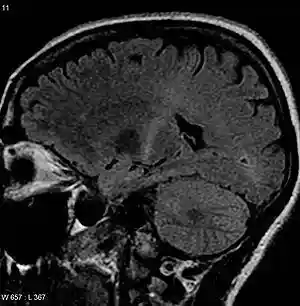

ALS Coronal.jpg

An MRI of the brain with increased T2 signal in the posterior part of the internal capsule that can be tracked to the motor cortex, consistent with the diagnosis of ALS